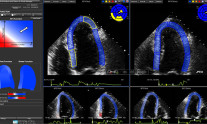

Η χημειοθεραπεία και οι άλλες θεραπείες για τον καρκίνο του μαστού αυξάνουν τον κίνδυνο καρδιοπάθειας

Η χημειοθεραπεία και οι άλλες θεραπείες για τον καρκίνο του μαστού μπορεί να αυξήσουν τον κίνδυνο καρδιοπάθειας, όπως καρδιακή...